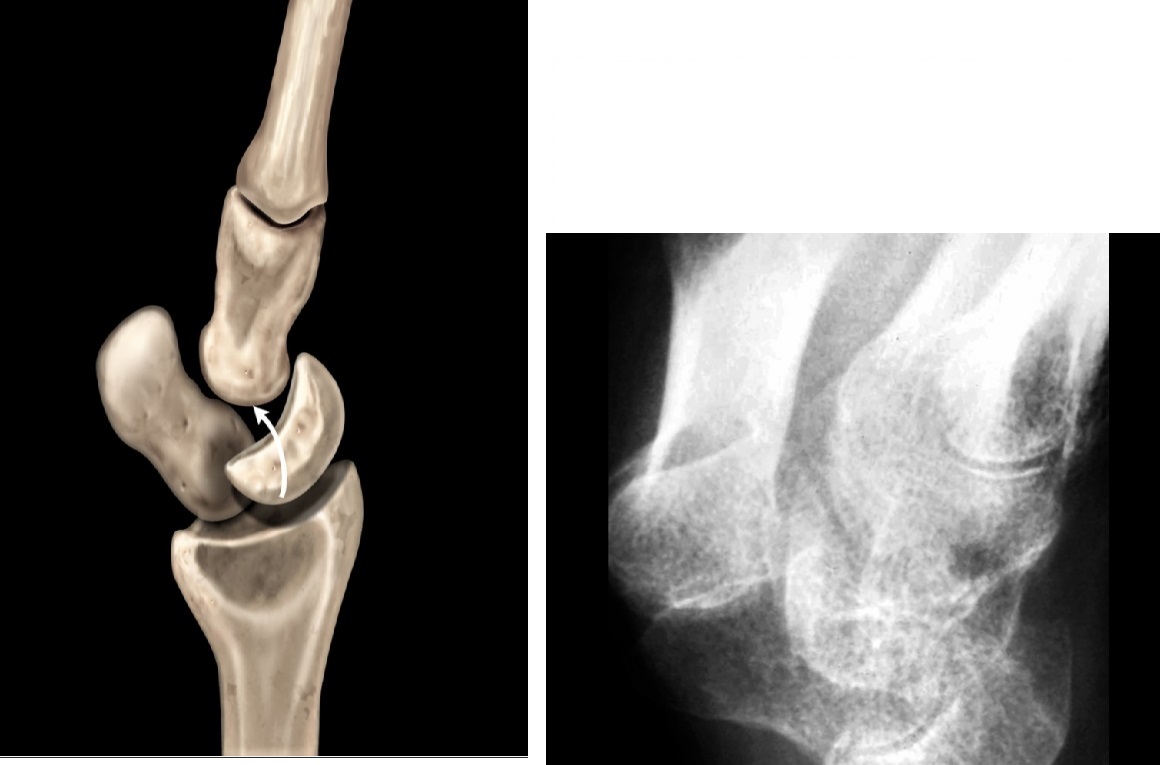

Gamekeepers

Avulsion fracture of the base of the proximal first phalanx

Ulnar collateral ligament disruption

STENER lesion = when adductor tendon gets caught in the torn edges of the UCL = Surgery